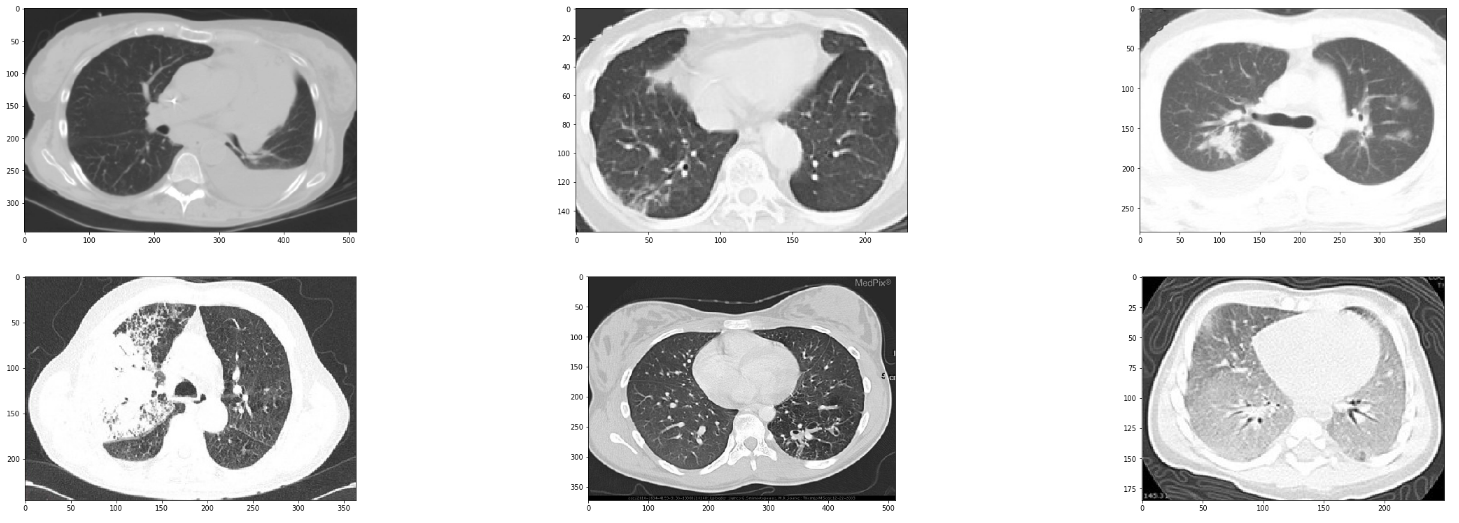

Before we start to build our classifier, let me make note of the structure of the data. We have the positive class with the scans of COVID-19 positive patients, whereas the negative class contains a mixture of healthy patients, and patients suffering from other (non-COVID-19) diseases that may cause opacities in the lungs.

In order to train a robust classifier, we must have the information about the non-COVID-19 patients as well. This is important since doctors never send a person straight to get a CT scan. In fact, since pneumonia is a clinical diagnosis, people who are put under CT Scan will probably be suffering from one of the respiratory illnesses such as viral/bacterial pneumonia/strep, etc., already. We'd seldom see a healthy patient sent for a CT scan.

Therefore, a practical classifier would have to differentiate between, say, COVID-19 induced pneumonia and other types of pneumonia. However, the negative class in this dataset is mixed up and contains healthy lungs, as well as the lungs of patients suffering from other maladies such as cancer. So what's the point of saying this? The point is that you should take this classifier as one for educational purposes. However, any classifier you want to put out in the wild would require more differentiated data.

We can similarly see random samples of the non-corona cases by changing the value of covid_files_path variable to Images-processed/CT_NonCOVID.